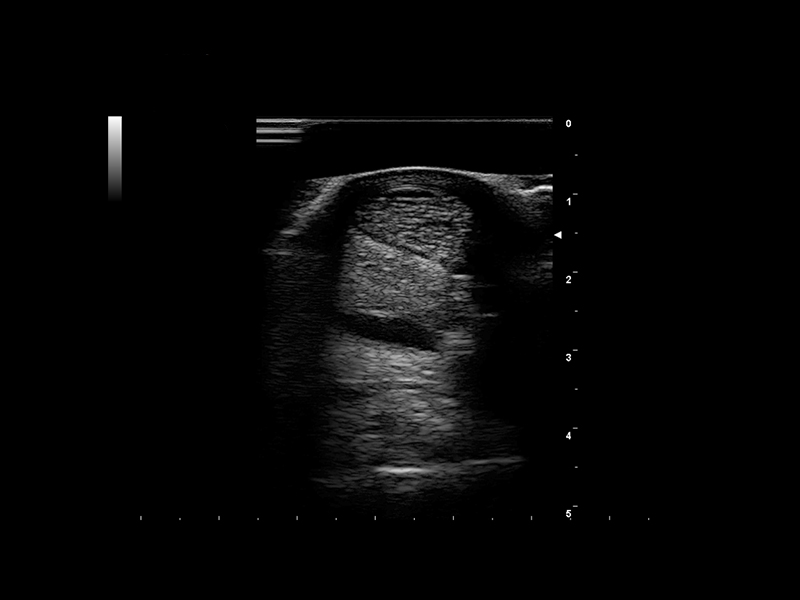

Equini - Immagine clinica - tendine 1

Equini - Immagine clinica - tendine 2

Equini - Immagine clinica - tendine 3

Equini - Immagine clinica - tendine 4

Equini - Immagine clinica - tendine 5

Equini - Immagine clinica - tendine 6

Equini - Immagine clinica - tendine 7

Equini - Immagine clinica - tendine 8

Equini - Immagine clinica - tendine 9

Equini - Immagine clinica - tendine 10

L'imaging muscoloscheletrico è tra le applicazioni più impegnative dell'ecografia negli esami degli equini. Il motivo principale è che le lesioni alle zampe sono comuni nei cavalli sportivi. Sono necessarie immagini di alta qualità, una penetrazione profonda e una risoluzione superficiale precisa per poter valutare con precisione infiammazioni e lesioni, formulare correttamente i piani di trattamento e garantire il benessere dei cavalli. Le tecnologieElaXto e QElaXto 2D, entrambe basate sull'elastografia a onde di taglio, offrono una soluzione semplice e affidabile per valutare l'elasticità di muscoli e tendini e pianificare il follow-up di recupero dopo gli infortuni.

L'eccellente imaging della vascolarizzazione di MicroVconsente anche di analizzare l'infiammazione. Inoltre, la penetrazione e la risoluzione non presentano più ostacoli grazie al trasduttore microconvex Esaote e alle sonde lineari con tecnologia XCrystal . Queste sonde, insieme alla vista trapezoidale (Esaote TPV), estendono il campo di scansione e consentono di acquisire immagini dettagliate raggiungendo le strutture vicine.